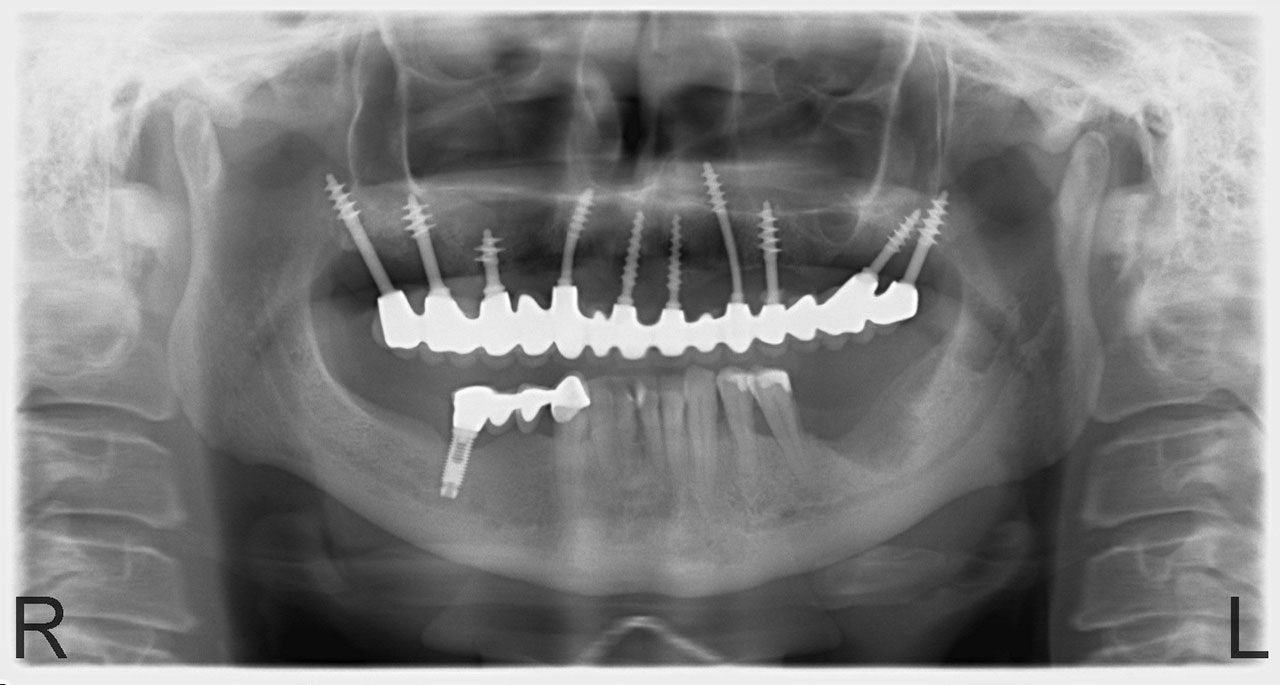

Így néz ki a hosszútávú ideiglenes híd.(Fém vázzal erősített műanyag híd.)

• esettanulmany-11

Szájban a hosszútávú ideiglenes híd.(Fém vázzal erősített műanyag híd.)

• esettanulmany-12

• esettanulmany-41

Így néz ki a hosszútávú ideiglenes híd. (Fém vázzal erősített műanyag híd.)

• esettanulmany-42

• esettanulmany-43

Így néz ki szájban a hosszútávú ideiglenes híd.(Fém vázzal erősített műanyag híd.)

• esettanulmany-44